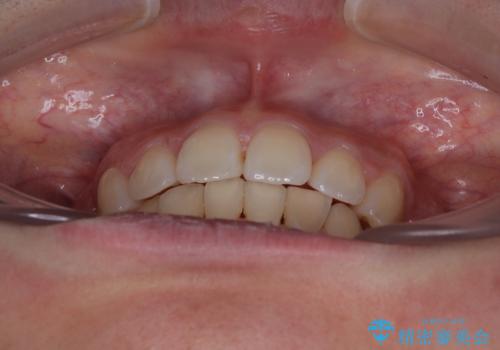

深い咬み合わせの改善に時間がかかりましたが、下顎前歯がしっかりと見えるまでに整えることができ、口元の突出感も大幅に改善することができました。